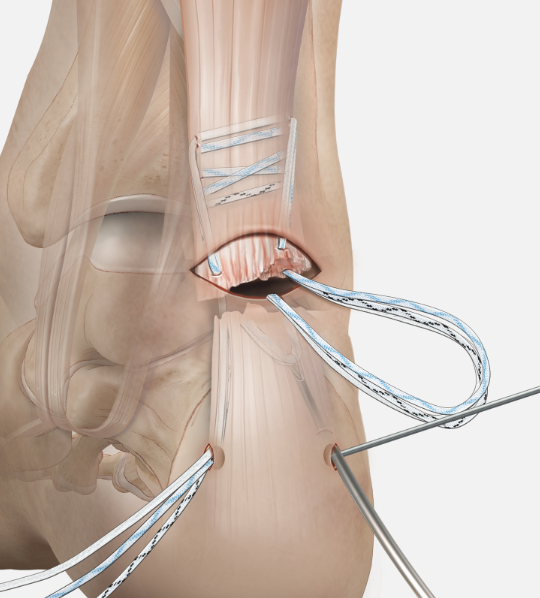

FHL transfer

Technique

Vumedi VY lengthening + FHL transfer video 1

Vumedi VY lengthening + FHL transfer video 2

Identify FHL tendon medially

- identify and protect tibial nerve

- pull tendon through and transect with sufficient length

- through drill hole in calcaneum and secure